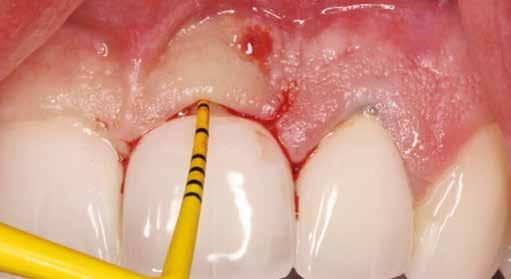

1. ábra: A műtét előtti szituáció, megfigyelhető az implantátumok közötti konkáv terület, ahova könnyen beragad az ételmaradék, és könnyen kialakul a periimplantitis.

Egy 47 éves páciens jelentkezett nálunk egy alsó, hátsó foghiánnyal, ahol jelentős csontfelszívódást tapasztaltunk a moláris fogak korábbi eltávolítása miatt (1. ábra). Két implantátum körül is volt ínyrecesszió, illetve a keratinizált íny mennyisége minimális volt (kevesebb, mint 1 mm). 4 hónappal az implantációt követően ínykorrekciót végeztünk.

2–5. ábra: A metszések és a deepitelizáció. – 6–9. ábra: Félvastag lebeny. – 10. ábra: A nyelezett ínylebeny „bepróbálása”.

horizontális metszéssel kötöttük össze (2–5. ábra). A metszések hosszát és a köztük lévő távolságot minden esetben a lágyszövet augmentációhoz szükséges keratinizált szövet határozza meg. A lebeny deepitelizációját egy 15C-s szikepengével végeztük (6. ábra). Ezt követően félvastag lebenyt preparáltunk (7. ábra). A lebenyt apikálisan, az alapjáról belső, felületes metszéssel felszabadítottuk, hogy passzívan áthelyezhessük és rögzíthessük, feszülés nélkül. Meziális irányba 180 fokkal átforgattuk (8–9. ábra). A meziális papillát alagúttechnikával (tunnelling technique) készítettük elő a graft befogadására (10. ábra). Az így kialakított lebenyt a recipiens ágyban rögzítettük az újonnan kialakított vesztibulum alapjánál 5-0 nem felszívódó PTFE (Coreflon, IMPLACORE) varratokkal. A graftot behajtottuk az ínyszél alá és meziális oldalon rögzítettük PTFE varratokkal (11–14. ábra)